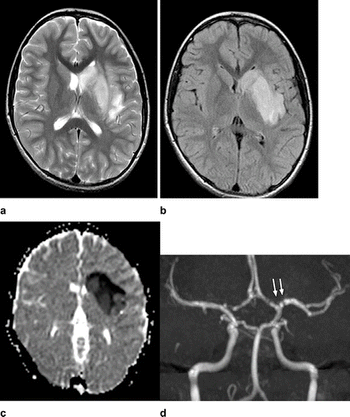

Case of acute necrotizing encephalopathy could be first of many.